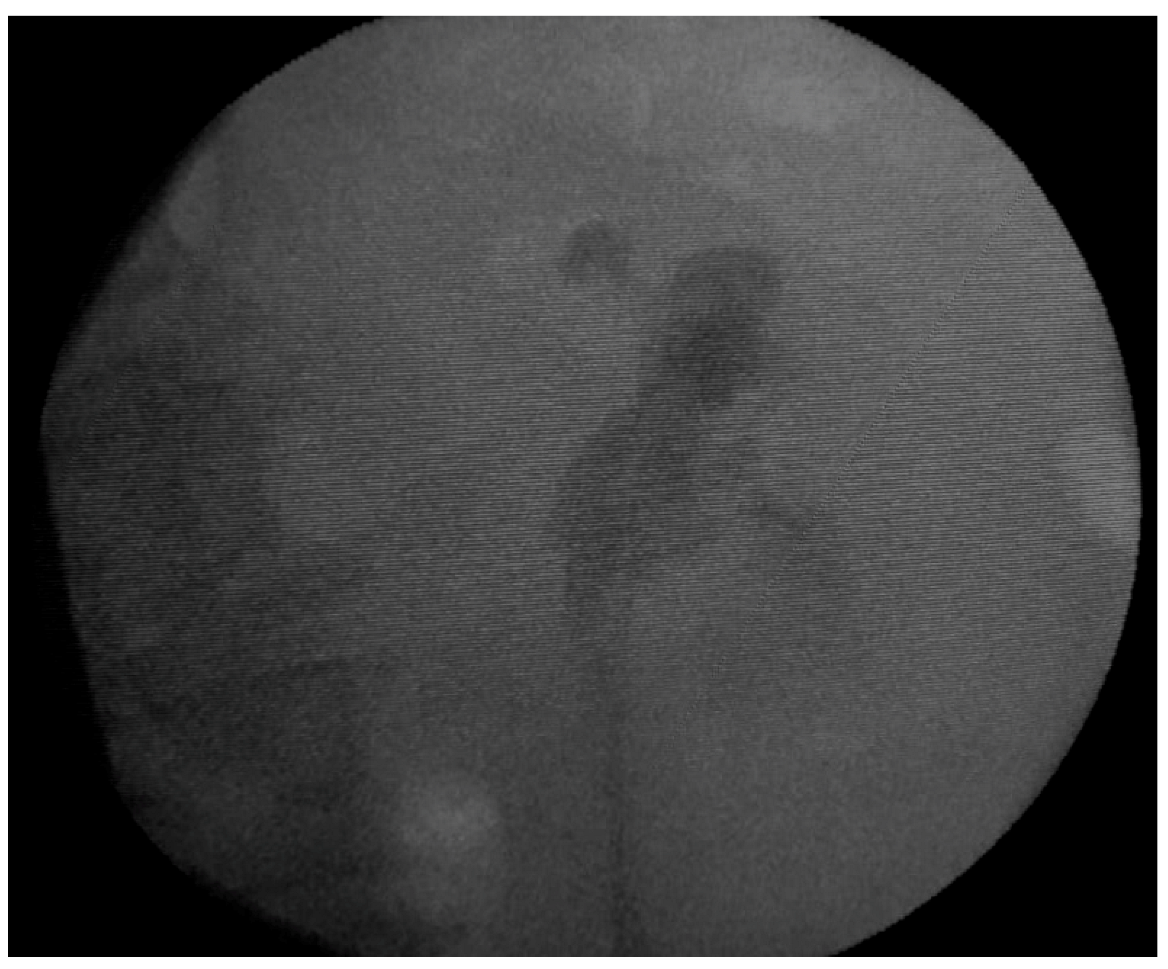

Emergency abdominal and pelvic non-contrast CT scan showed multiple thin left ureteral, pyelic, and calyceal calcifications on the surface of the urothelium, which are specific to encrusted uretero-pyelitis, with a maximum density of 510 Hounsfield units and with a mild dilation of the upper left urinary tract, right kidney hypoplasia, and enlarged retroperitoneal lymph nodes (Figure 1 and Figure 2).

Figure 2. Multiplanar reconstruction of abdominal and pelvic CT scans without contrast shows multiple ureteral, pyelic, and calyceal encrustations.